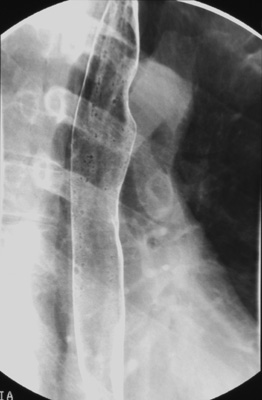

Rotate the patient into a left posterior oblique (LPO) position (to

rotate the spine away from overlapping with the esophagus).

Ask the patient

to drink 1/2 cup of "bubbly barium" quickly and tell him not to belch. Scan

the length of esophagus while the patient swallows. Obtain two

double-contrast spot images - one of the upper and one of

the lower esophagus (including the gastric cardia) during maximal gas distention

after all gas bubbles have disappeared. Collimate the fluoroscopic image side-to-side before taking the esophageal spot images.